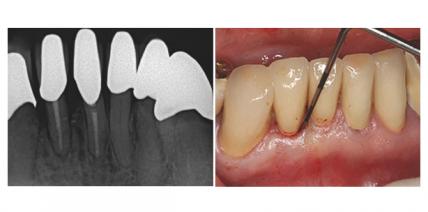

Therapie komplexer Paro-Endo-Läsionen

Für eine erfolgreiche Behandlung von Paro-Endo-Läsionen ist ein spezielles Therapiekonzept erforderlich. Am Beispiel von zwei Fällen wurden erfolgreiche Behandlungen bei kombinierten Paro-Endo-Läsionen belegt, bei denen neben ­parodontalchirurgischen Maßnahmen auch GBR-Techniken zur Anwendung kamen. weiterlesen